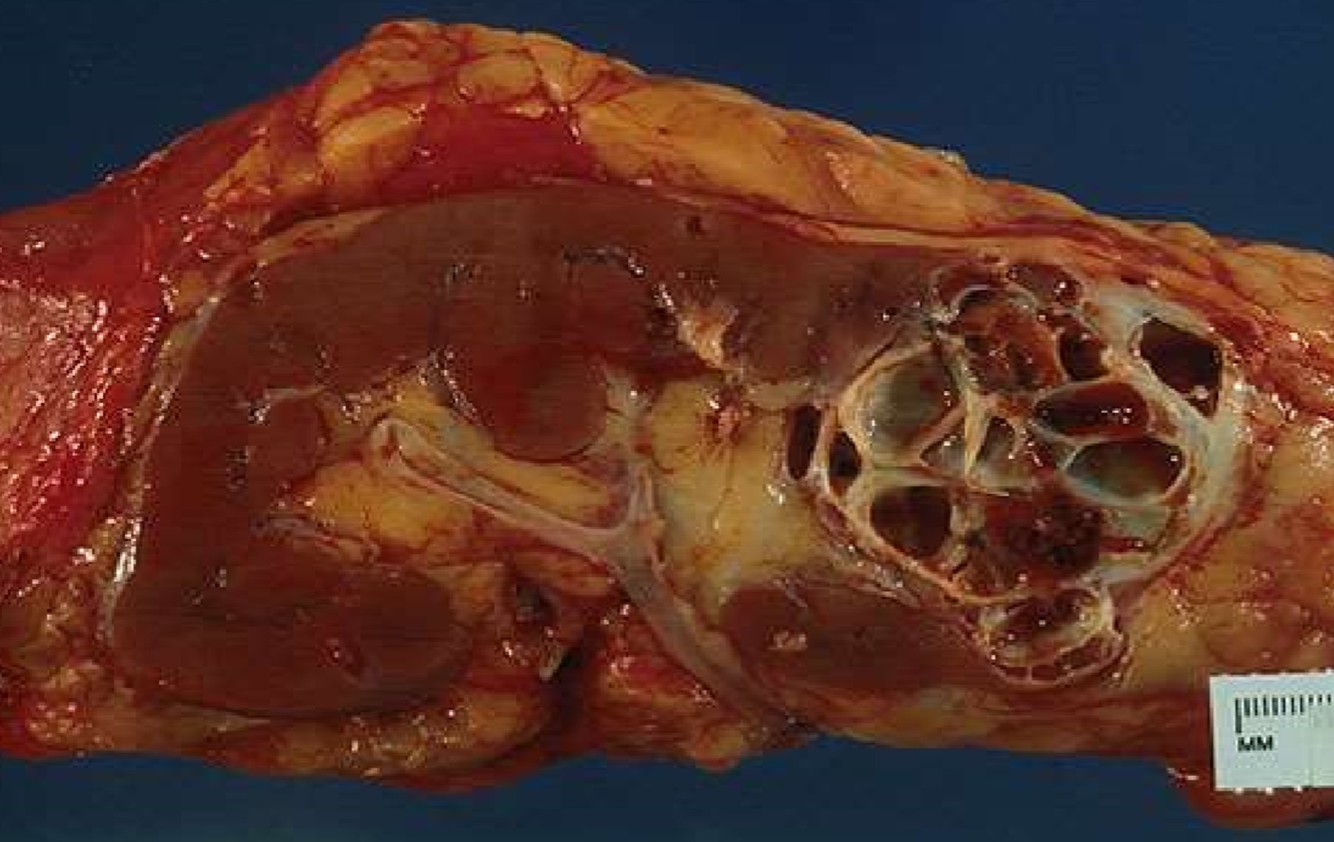

CYSTIC NEPHROMA

- Presents as a multilocular renal cyst

- Bimodal in age distribution: children less than 4 years of age, young women

- Excellent prognosis

MULTILOCULAR CYSTIC RCC

- Presents as a multilocular renal cyst

- Excellent prognosis; classified by the WHO as a neoplasm of low-malignant potential